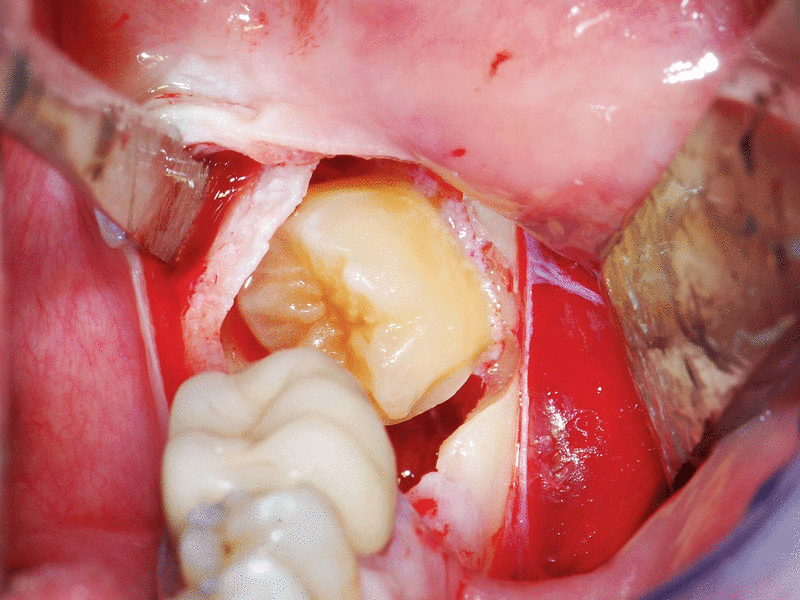

Zur Koronektomie

Bezüglich der Koronektomie haben sich im Zeitraum der Aktualisierung keine wesentlichen neuen Erkenntnisse ergeben. Der Umfang der Verlaufsbeobachtungen hat sich zwar gebessert und es werden komplikationsarme Nachbeobachtungszeiten über Zeiträume bis hin zu mehr als fünf Jahren beschrieben, es fehlen aber weiterhin Daten zu den längerfristigen Auswirkungen über die Lebensspanne der Patienten, beispielsweise bei einer späteren Therapie mit Antiresorptiva, bei Immunsuppression, Diabetes, Dialyse, Tumortherapie und vielen mehr. Insofern bleibt die Koronektomie weiter eine Behandlungsalternative mit engen Grenzen in der Indikationsstellung.

Empfehlung:Als Alternative zur vollständigen Zahnentfernung kann bei enger Lagebeziehung zum N. alveolaris inferior mit erwartbar hohem Schädigungsrisiko eine Koronektomie vor-genommen werden.

Hintergrund:In den letzten Jahren ist die Methode der selektiven Kronenentfernung unter Belassen der Wurzel des Weisheitszahns neu aufgegriffen worden. Diesem Behandlungskonzept liegt die Überlegung zugrunde, bei hohem Risiko einer Verletzung des N. alveolaris inferior auf die vollständige Wurzelentfernung zu verzichten und allein die Krone und das Follikelgewebe des Weisheitszahns als Ursache der Perikoronitis zu beseitigen. Mittlerweile wurden einige Fallserien, mehrere vergleichende Kohortenstudien [Cilasun et al., 2011; Hatano et al., 2009; O´Riordan, 2004; Pogrel et al., 2004] und auch prospektiv randomisierte Studien [Leung and Cheung, 2009; Renton et al., 2005] vorgestellt, die erwarten lassen, dass das Risiko der Schädigung des N. alveolaris inferior durch die Koronektomie vermindert wird. Allerdings sind die langzeitigen Folgen des Belassens von Zahnanteilen, beispielsweise im Hinblick auf eine spätere Bestrahlung oder antiresorptive Behandlung oder auch eine therapeutische Immunsuppression bislang nur unzureichend untersucht. Über einen Nachbeobachtungszeitraum von bis zu fünf Jahren wurden allerdings bislang nur sehr geringe Sekundärkomplikationen beobachtet [Leung und Cheung, 2016].

Mittlerweile wurden neben der klassischen Koronektomie auch Modifikationen, wie eine geplante zweizeitige Entfernung nach Teilentfernung der Zahnkrone [Landi et al., 2010], nach Teilentfernung des Knochens [Tolstunov et al., 2011] oder ergänzt durch kieferorthopädische Maßnahmen [Wang et al., 2012] oder Guided Bone Regeneration [Leung, 2016] beschrieben. Für die jeweiligen Modifikationen liegen aber bislang nur Erkenntnisse aus kleinen Patienten-Kohorten vor.